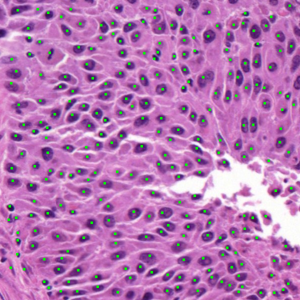

Dataset 2, released as supplementary material in [73], contains 36 digitized H&E-stained microscopy images (600 × 600 pixels) with 7931 nuclei annotated by three expert pathologists; only consensus annotations are retained. It is designed for cell nuclei detection.

Dataset 3 consists of 50 annotated H&E-stained histological images from triple-negative breast cancer patients [74]. The images were acquired at 40× magnification using a Philips Ultra Fast Scanner (1.6RA) at the Curie Institute and contain a total of 4022 annotated cells.

Representative samples from the three datasets are shown in Fig. 1. In (a), the first frame of the synthetic video in Dataset 1 illustrates the strong illumination gradients produced by distance-dependent shading together with orientation-dependent interactions between vertex normals and the light direction. The H&E images in (b) and (c), also from Dataset 1, depict a mast cell infiltrate from a patient with non-alcoholic steatohepatitis and cirrhosis and, respectively, a sample from a patient with sclerosing polycystic adenosis of the parotid gland; the former consists primarily of purple nuclei, white cytoplasm, and pink extracellular tissue. Subfigures (d) and (e) show two examples from Dataset 2 accompanied by their ground-truth nuclei annotations, while (f) and (g) present a representative image from Dataset 3 together with its corresponding cell mask.

Figure 1: Samples from Datasets 1–3. (a) First frame of the 74-frame video in Dataset 1 (1770 × 880) with a superimposed red mesh. (b,c) H&E-stained tissue images from Dataset 1 (1000 × 750; 950 × 730). (d,e) Cell images from Dataset 2 (600 × 600) with nuclei annotations. (f,g) Image from Dataset 3 (512 × 512) with annotation.

7.2 Quantitative Results

We now assess SP using the 36 images from Dataset 2 and 50 images from Dataset 3. In our evaluation, we employ the Dice similarity coefficient (DSC) (as usual defined as the harmonic mean of precision and recall), DSC=2/(1/precision+1/recall),\mathrm{DSC}=2/(1/\mathrm{precision}+1/\mathrm{recall}), precision=tp/(tp+fp),\mathrm{precision}=\mathrm{tp}/(\mathrm{tp}+\mathrm{fp}), recall=tp/(tp+fn),\mathrm{recall}=\mathrm{tp}/(\mathrm{tp}+\mathrm{fn}), where tp\mathrm{tp} denotes the number of ground-truth points within the segmentation foreground, fp\mathrm{fp} the number of predicted regions without ground truth, and fn\mathrm{fn} the number of ground-truth points outside the segmentation foreground [73]. In Dataset 3, since pixel-level annotations were given [74], the above metrics were calculated on a per-pixel basis.

Table 1, on Dataset 2, shows that SP obtained the highest DSC (88.78), which is higher by 5.90, 7.09, 8.31, and 22.46 compared to SAM, ZZ, SMST, and AR, respectively. The segmentation time of SP was 14.55s, approximately twice that of SAM (the second fastest method without considering pre-processing times), and more than one order of magnitude lower than the level-set methods AR and ZZ. While AR and ZZ need user-specific markers as input (the pre-processing time indicated as \infty), SAM needs to load the pre-trained model (6.09s) while SP and SMST need to generate the superpixels in the pre-processing step (0.08s). Figure 11 shows the resulting segmentations for two example images from Figs. LABEL:fig_sub:he3_image and LABEL:fig_sub:he4_image from Dataset 2. The segmentations reflect the trends observed in Table 1, with SP achieving the highest DSC and segmentation times exhibiting a similar relative order.

On Dataset 3, the resulting DSC values, shown in Table 1, are lower than those for Dataset 2. This difference is mainly caused by the fact that Dataset 3 provides pixel-level annotations, whereas Dataset 2 only includes nuclei center annotations. The computation times for AR and ZZ are shorter due to the smaller image size (512×512512\times 512 vs. 600×600600\times 600 in Dataset 2). SP achieves a DSC improvement of 3.62 over SAM, despite being roughly twice as slow as SAM in the segmentation process. The results also show that SP achieves again the highest DSC performance (76.62), outperforming SMST (DSC 60.63), AR (DSC 61.35), and ZZ (DSC 65.33).